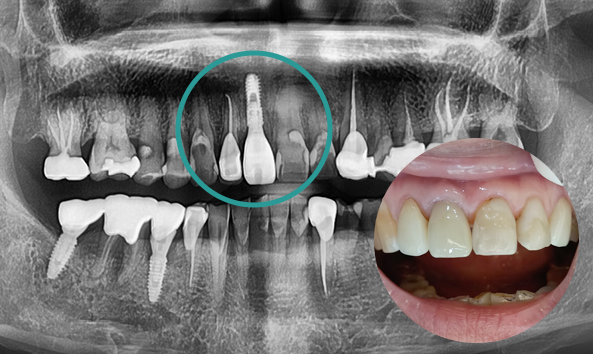

본래 내 치아처럼,

자연스러운 앞니 임플란트

임플란트의 안정성과 심미적인 부분을

모두 고려해야 하는 앞니 임플란트!

어금니보다 공간이 좁고 뼈가 얇기 때문에

정확한 각도와 방향으로 식립 되어야 합니다.

고난도 과정인 앞니 임플란트!

심미와 안정성 모두 약속드립니다.

정밀한 잇몸뼈 상태 확인

앞니 임플란트를 진행하려는 부위에 잇몸뼈가 퇴축되어 있다면 심미적인 문제가 발생할 수 있습니다. 이런 경우, 시술 전 잇몸뼈 이식 수술로 잇몸뼈를 보강한 후 임플란트를 진행해야 합니다.

자연스러운 보철물 제작

치아 보철물에는 다양한 종류가 있습니다. 내부에 메탈이 포함된 보철물과 투명도가 높은 보철물이 있으며, 심미성에 차이가 있는 만큼 환자의 특성과 필요에 맞는 보철물을 선택합니다.

당일 수술 후 임시보철물 완성

앞니는 심미적인 요인과 연결되는 만큼 당일 수술 후 원내에서 바로 임시보철물을 제작하여 일상생활 하실 때 문제 없으시도록 도와드립니다.